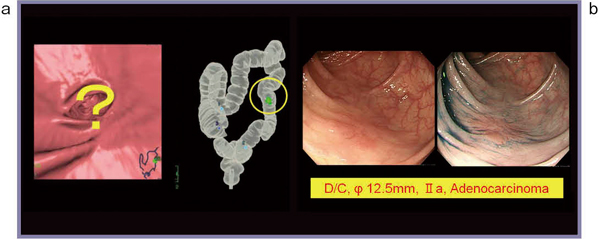

■症例3:46歳,女性

便潜血検査陽性で大腸内視鏡検査を施行したが,異常なしとされた。しかし,同日に施行した大腸CTにおいて,肝彎曲部に30mm程度の表面型病変が指摘され(図3a),後日,再度内視鏡検査を行った。大腸CTで指摘された部位を何度も往復してようやく同様の病変を指摘し(図3b),ESD(内視鏡的粘膜下層剥離術)を施行した。

図3 症例3

a:大腸CTの内腔像 b:内視鏡像